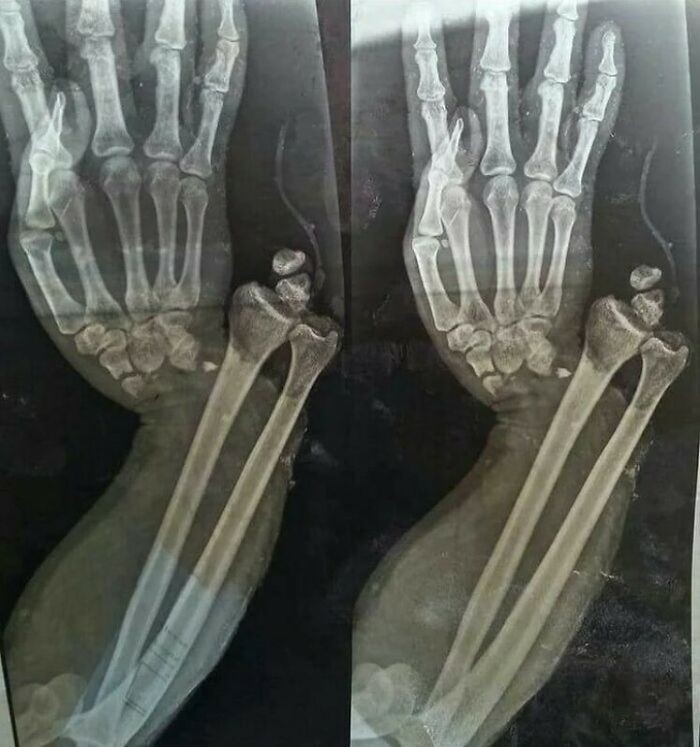

Fraktur dislokasi terbuka pada pergelangan tangan Foto: Boredpanda